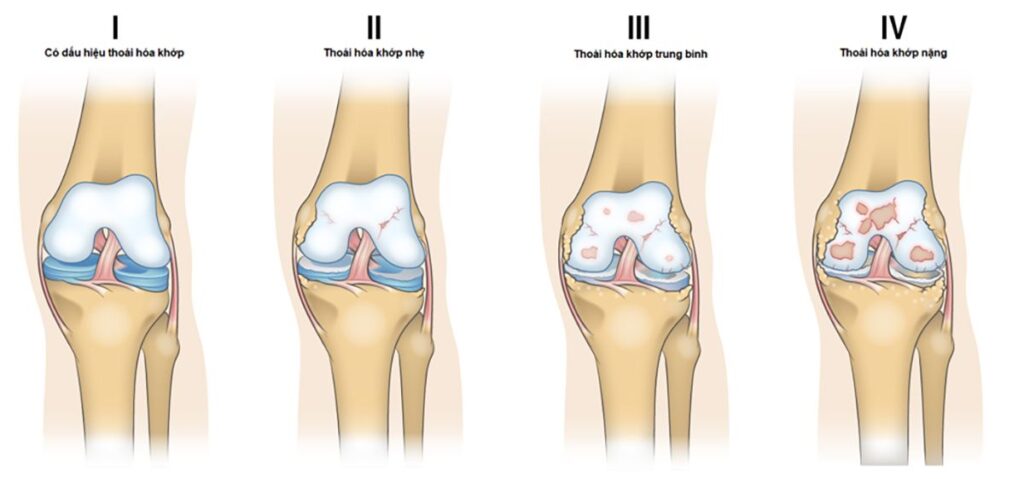

Thoái hóa khớp gối được chia thành 4 giai đoạn với các triệu chứng và dấu hiệu riêng biệt.

Giai đoạn 1: Có dấu hiệu bệnh

Trong giai đoạn này, khu vực đầu gối không có biểu hiện rõ ràng. Tình trạng mài mòn giữa các thành phần của khớp vẫn diễn ra bên trong nhưng không gây cảm giác sưng, nhức hay đau đớn cho người bệnh.

Giai đoạn 2: Mức độ bệnh nhẹ

Đến giai đoạn 2, người bệnh mới bắt đầu có các triệu chứng cụ thể như đau nhức sau một ngày dài sử dụng chi dưới nhiều, dễ bị cứng khớp hoặc đau khi quỳ, cúi hoặc không cử động đầu gối trong vài giờ liên tục.

Đây được coi là giai đoạn nhẹ của bệnh thoái hóa khớp vì không gian giữa các xương chưa bị thu hẹp lại. Chất dịch tiết ra từ khớp vẫn đủ để các xương không bị cọ xát với nhau.

Giai đoạn 3: Mức độ trung bình

Khi chụp X-quang có thể thấy sụn giữa các xương có dấu hiệu bị tổn thương, gây sưng, đau hoặc cứng. Không gian giữa các khớp gối bắt đầu thu hẹp lại, khiến người bệnh cảm thấy khó khăn khi đi bộ, chạy, cúi, quỳ… Triệu chứng cứng khớp ở giai đoạn 2 cũng diễn ra ở giai đoạn 3 nhưng với tần suất thường xuyên hơn, nhất là sau khi ngồi một thời gian hoặc thức dậy vào buổi sáng.

Giai đoạn 4: Mức độ nghiêm trọng

Bệnh thoái hóa khớp gối ở giai đoạn 4 được đánh giá là nghiêm trọng, khi bất cứ cử động nào cần sử dụng đến khớp đều gây đau nhói, khó chịu. Giai đoạn này không gian giữa các xương bị thu hẹp đáng kể. Phần sụn lúc này không chỉ bị mài mòn, biến dạng mà còn thường xuyên bị cứng hoặc bất động đo thiếu hụt trầm trọng lượng chất dịch giúp các đầu khớp giảm ma sát với nhau.